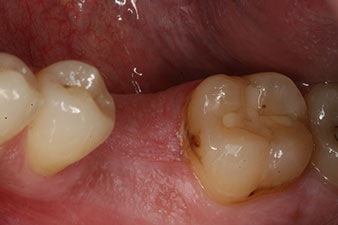

The final pictures show the screw-retained monolithic composite crown in place and the x-ray check (Fig. 9 and 10) (6).

composite crown

Fig. 9: The final composite crown was cemented on a PEEK hybrid abutment in the laboratory and can be screwed in place immediately.